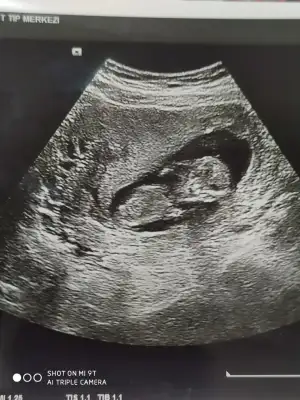

12 haftalık USG bu çok teşekkür ederimDiğer taraftaki konumda yazdim erkek gibi sanki tekrar USG paylasin

Başka USG paylaşın12 haftalık USG bu çok teşekkür ederim![]()

8 haftalık budaBaşka USG paylaşın![]()

Karından ise erkek vajinalsa kiz tabiki en iyi 11 12 13 haftalar8 haftalık buda